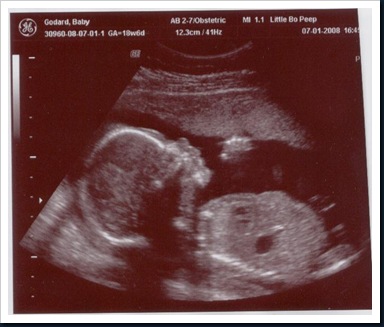

...Three boys that is. This is a sonogram of the newest addition to our family! I think Nate will really enjoy having a little brother to be his buddy.